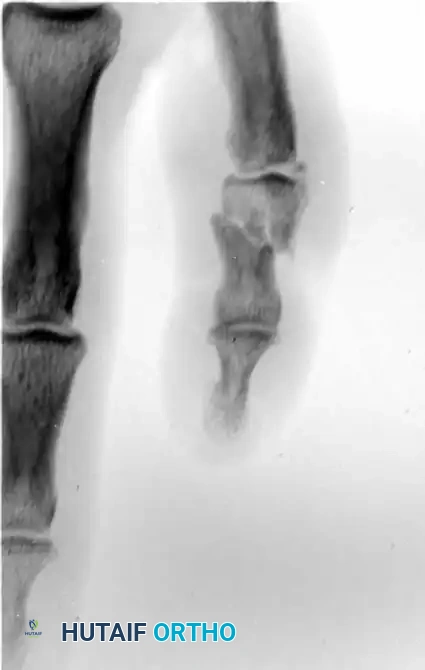

Fracture-Dislocations of the Proximal Interphalangeal (PIP) Joint

Fracture-dislocations at the PIP joint typically result in an unstable dorsal displacement of the middle phalanx. This is caused by the disruption of the volar plate's attachment to the volar lip of the middle phalanx, often accompanied by impaction of the articular surface.

Treatment is strictly dictated by the percentage of articular surface involved and the degree of comminution.

1. Large Volar Fragment (>50% of Joint Surface)

If a large, single volar fragment involving more than 50% of the joint surface is present, the joint is highly unstable. Open reduction and internal fixation (ORIF) is required. This can be achieved with miniature lag screws, K-wires, or a wire loop pull-out technique to secure the fragment and restore the volar buttress.